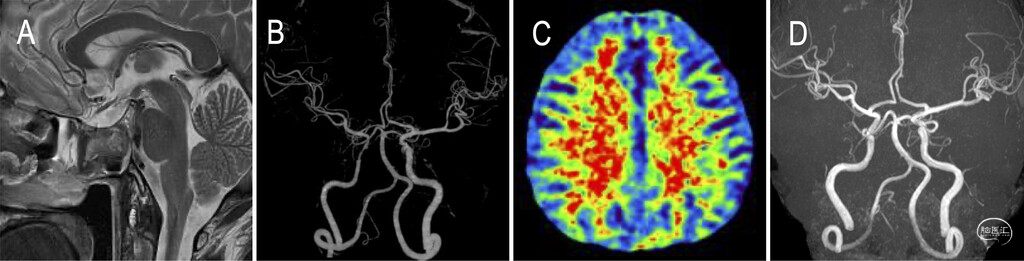

术后2-3天,患者视野缺损及动眼神经麻痹症状完全缓解。术后次日MRI检查示肿物已充分缩小(图4A),MR血管造影显示右侧颈内动脉狭窄情况迅速改善(图4B)。术后第4天CT灌注血管成像结果显示,右侧大脑中动脉供血区的平均通过时间(MTT)延长情况亦有所好转(图4C)。患者于术后第8天病情稳定出院。术后第15天眼科检查显示,患者右眼暗点消失,右侧动眼神经麻痹症状得到改善。术后3个月随访时,影像学检查未发现病变复发迹象,且右侧颈内动脉狭窄情况持续改善(图4D)。

图4:A:术后T2加权MRI示肿物已完全清除。B:术后MR血管造影示右侧颈内动脉狭窄显著改善。C:术后CT灌注成像示双侧大脑半球MTT无灌注差异。D:术后3个月MR血管造影示右侧颈内动脉狭窄完全解除。